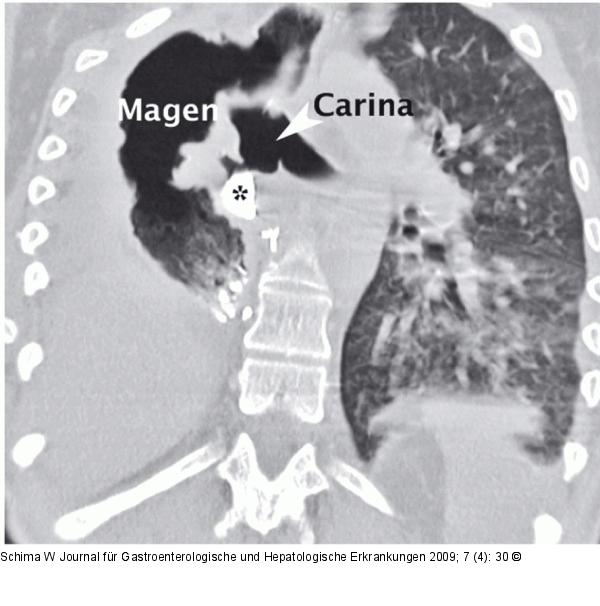

Abbildung 2a: Gastro-bronchiale Fistel Die CT (koronale Schnittebene) nach Videocinematographie zeigt einen Kontrastmittelübertritt in den rechten Hauptbronchus (Stern), jedoch nicht die Fistel |

Die CT (koronale Schnittebene) nach Videocinematographie zeigt einen Kontrastmittelübertritt in den rechten Hauptbronchus (Stern), jedoch nicht die Fistel |